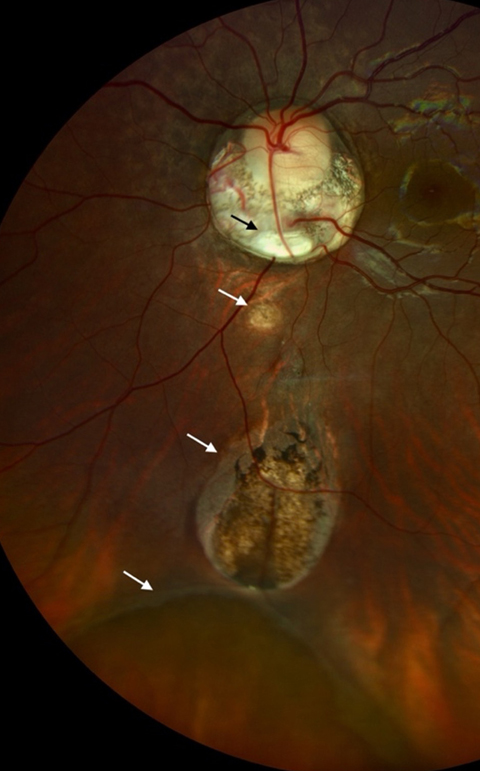

A quadruple fundal coloboma